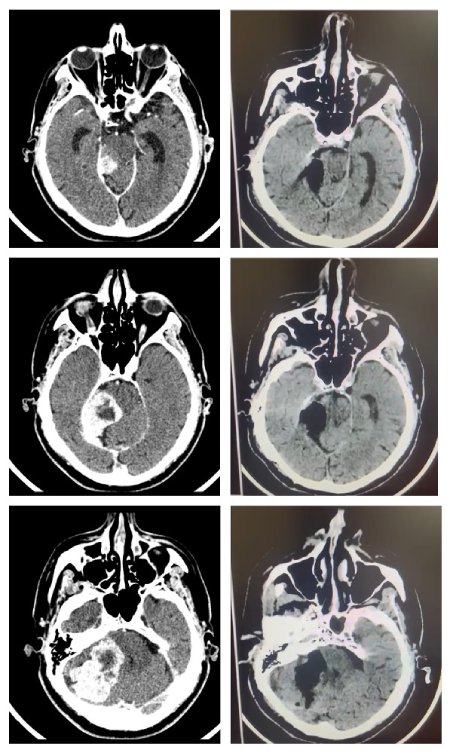

МРТ головного мозга до и после операции